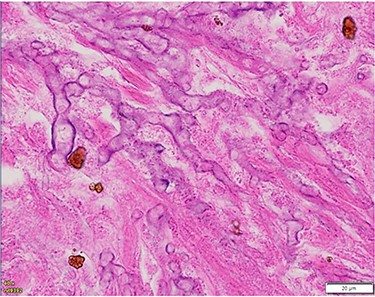

The patient underwent a left-sided temporal lobectomy to excise the lesion but, due to the proximity to the cavernous sinus, the lesion was not followed beyond the dural attachment on the middle fossa floor. Unexpectedly, the histopathology revealed hyphae resembling a zygomycete, with broad (5–12 μm) hyphae without septae and branching angles between 45° and 90° (Fig. 2). Liposomal amphotericin B treatment was initiated at 5 mg/kg per day and later increased to 10 mg/kg per day. Fungal cultures yielded no growth.

Histopathology of left temporal lobe lesion resembling zygomycete but later confirmed A. fumigatus.